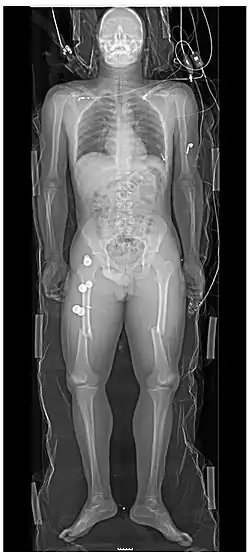

Les personnes ayant subi un traumatisme majeur ont souvent des radiographies du thorax et du bassin[22] et, selon le mécanisme de la blessure et la présentation, une évaluation ciblée avec échographie à la recherche d'hémorragie interne (FAST écho : focused assessment with sonography for trauma). Pour ceux qui ont une pression artérielle, une fréquence cardiaque et une saturation en oxygène relativement stables, les tomodensitogrammes sont utiles. Les tomodensitogrammes du corps entier, appelés body-scan, améliorent le taux de survie de ceux qui ont subi un traumatisme majeu[23],[24]. Ces scanners du corps entier (ou body-scan) utilisent des injections intraveineuses par produit de contraste (agent radioactif)[25]. On craint que l'administration de produit de contraste intraveineux dans des situations de traumatisme sans confirmation d'une fonction rénale adéquate puisse endommager les reins, mais cela ne semble pas être significatif[26].

Aux États-Unis, la tomodensitométrie ou l'IRM sont effectuées sur 15% des personnes ayant subi un traumatisme dans les services d'urgence[27]. Lorsque la pression artérielle est basse ou que la fréquence cardiaque augmente — probablement à cause d'un saignement dans l'abdomen — une intervention chirurgicale immédiate en contournant un scanner est recommandée[28]. Les tomodensitogrammes modernes à 64 coupes peuvent exclure, avec un haut degré de précision, des blessures importantes au cou après un traumatisme contondant[29].